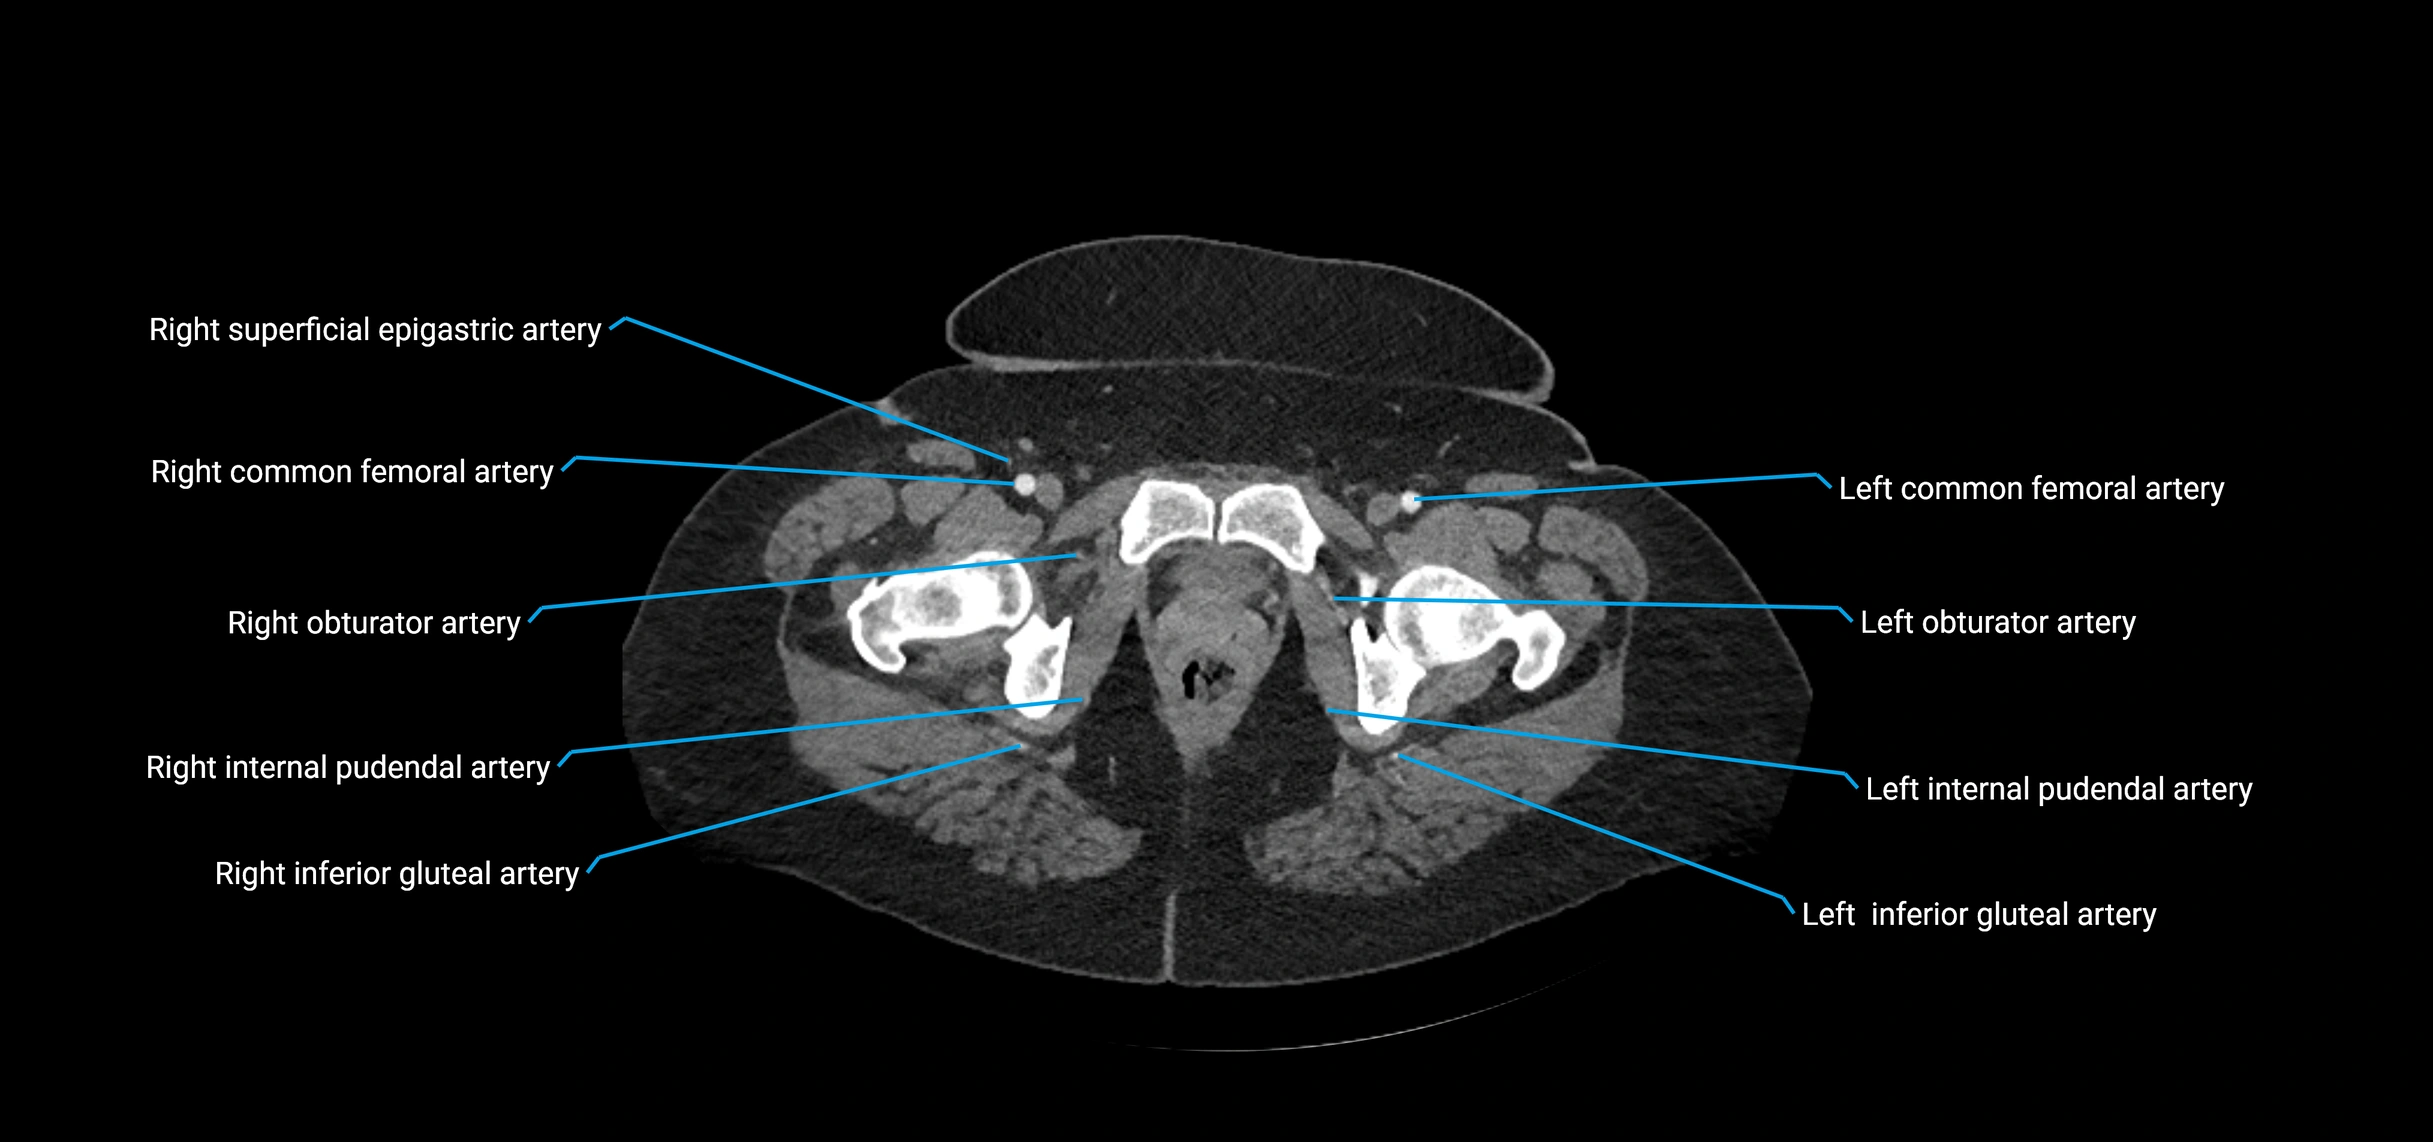

CT images

image

Contrast-enhanced CT (CTA):

• Gold standard for abdominal aortic imaging

• Provides excellent detail of lumen, wall, aneurysm, thrombus, and branch vessels

• Multiplanar and 3D reconstructions help in aneurysm measurement, stent graft planning, and dissection evaluation